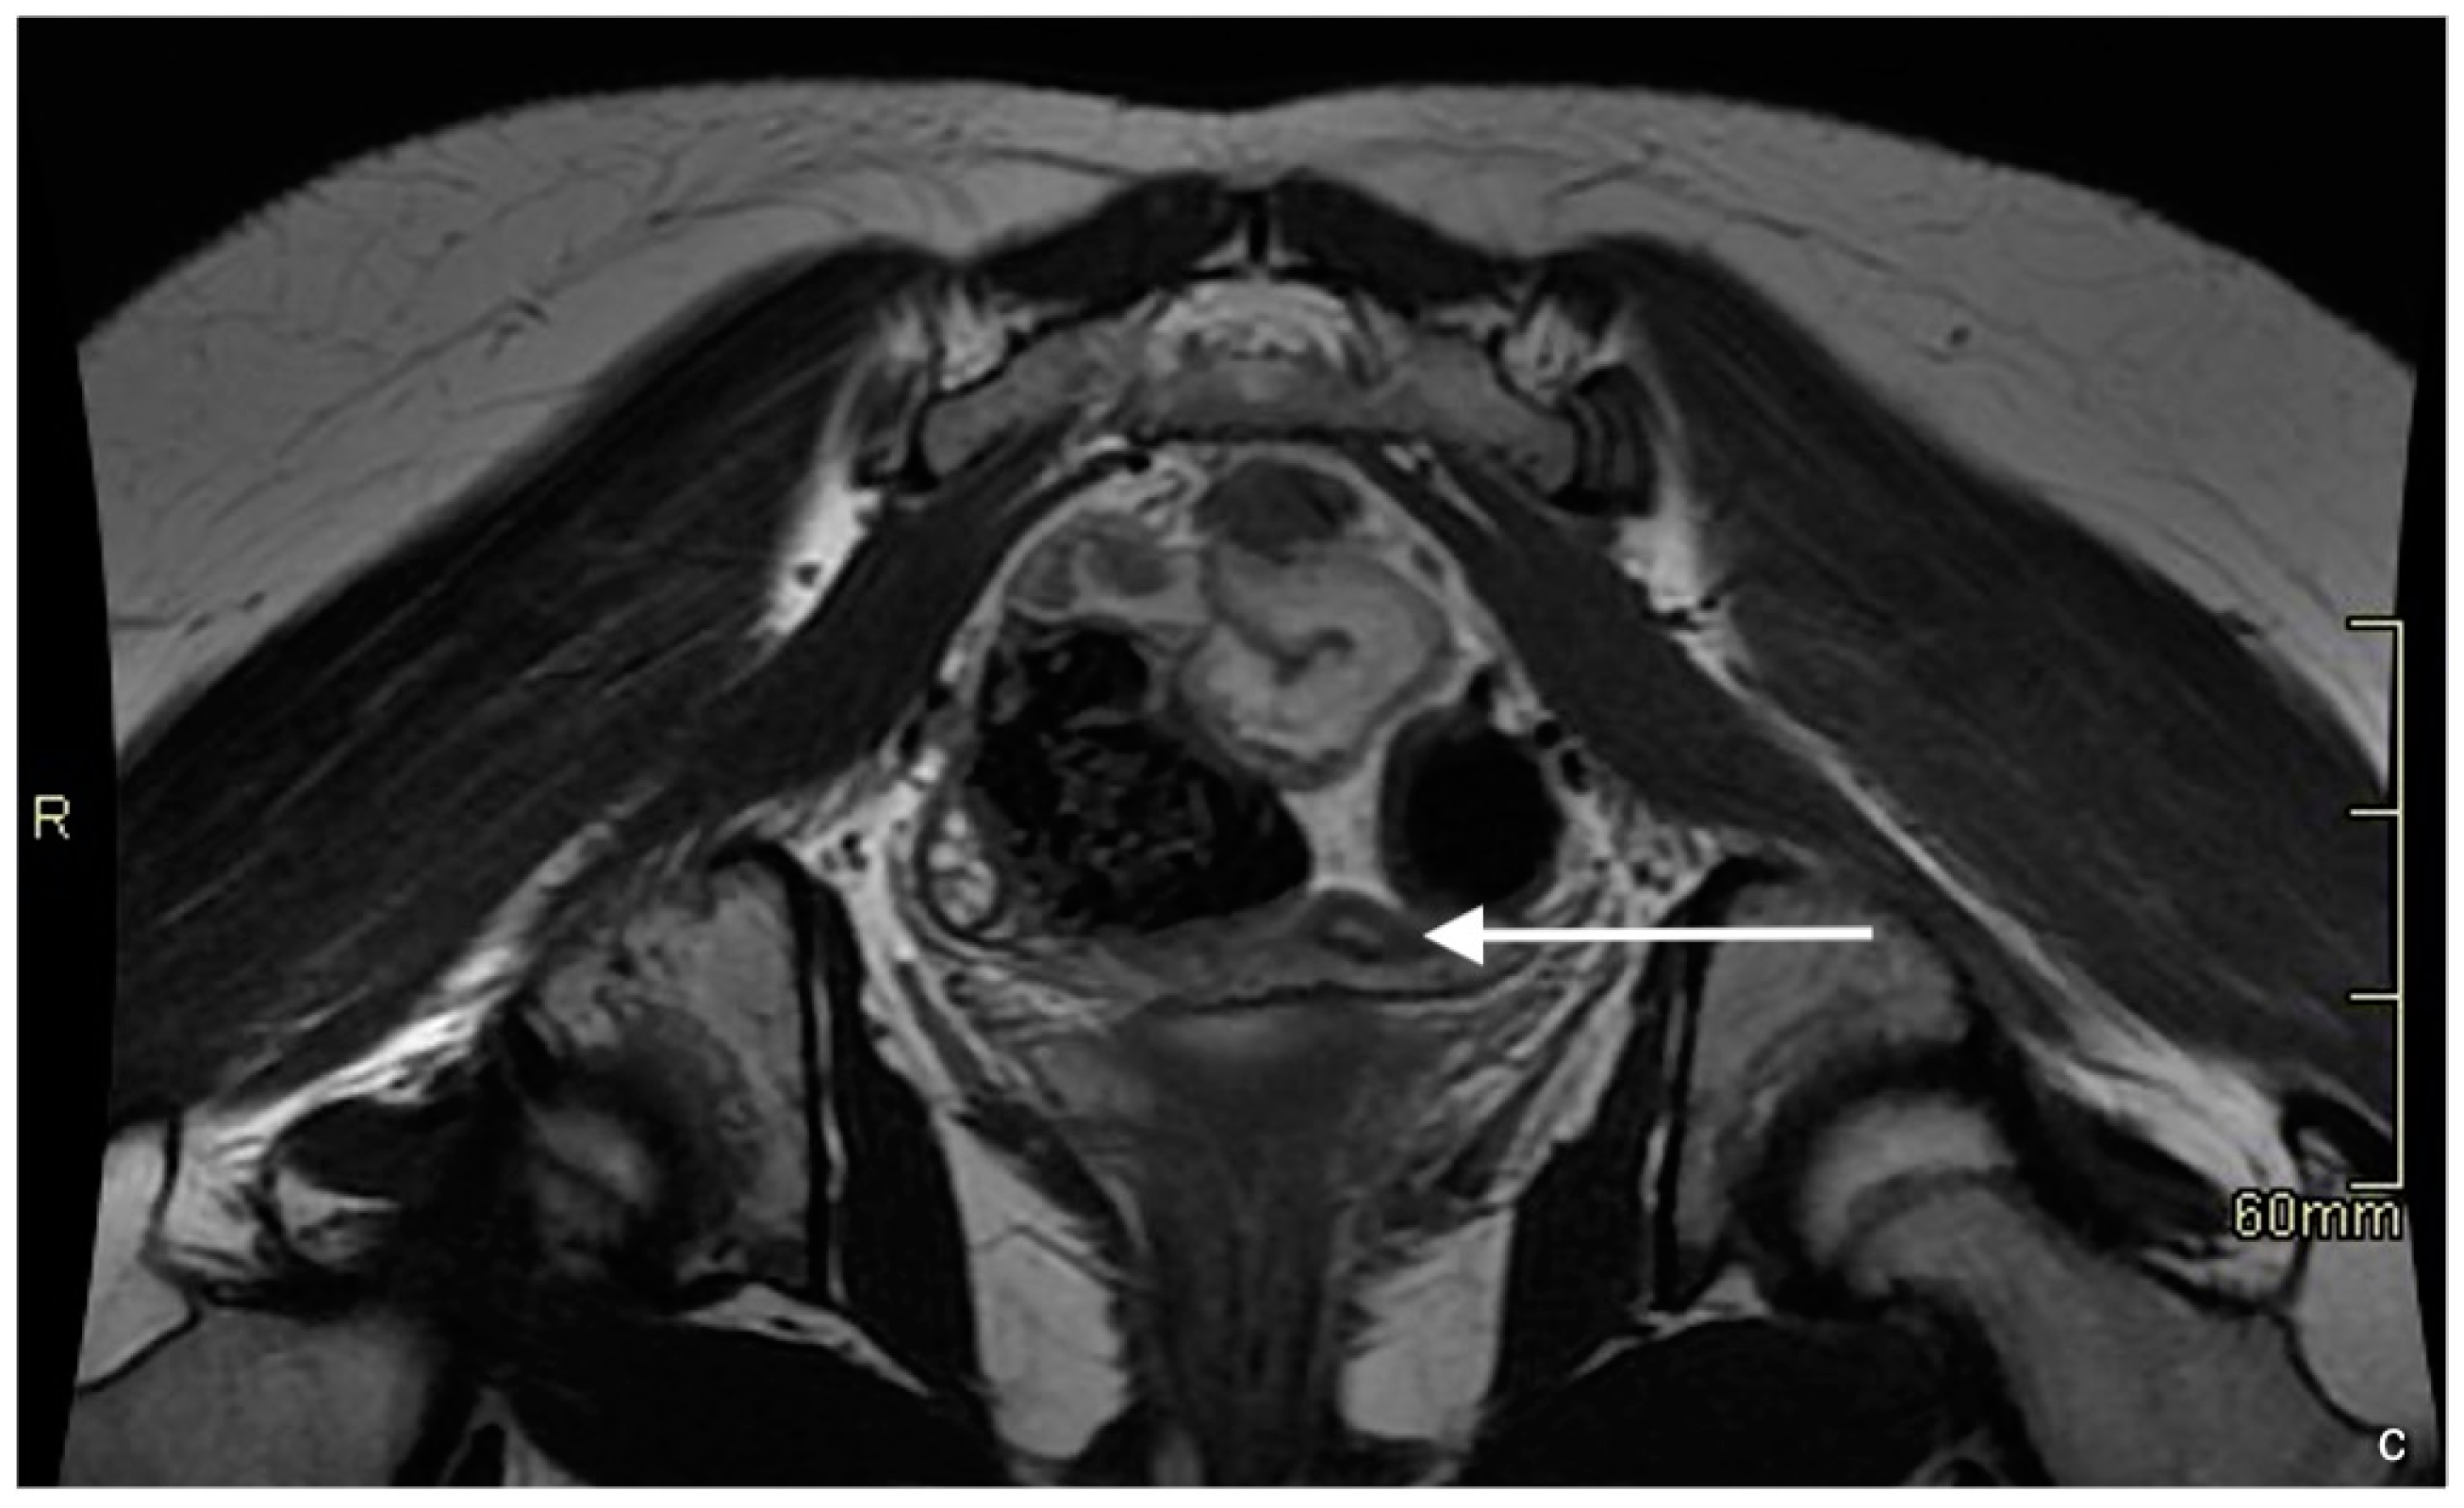

3. Case 2

| MRI report on primary investigation | Absent uterus, impression of hypoplastic vagina. Normal multicystic ovaries | Absent uterus and presence of a short vagina. Normal ovaries | Normal multicystic ovaries and a small uterus of 2.3 × 1.3 cm, described as rudimentary uterus | |

| MRI after referral | Lipofibromatous tissue at location of the uterus, no endo- myometrial or cervical structures. Normal multicystic ovaries | Underdeveloped Müllerian structures. Gonads with (ovo)testicular aspect | Small uterus with normal endo- and myometrial tissue, normal multicystic ovaries | |